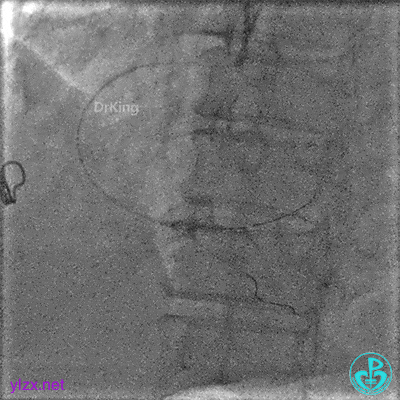

1周后复查冠脉造影

PL主支通畅,远端一个小分支丢失,未见破口存在。